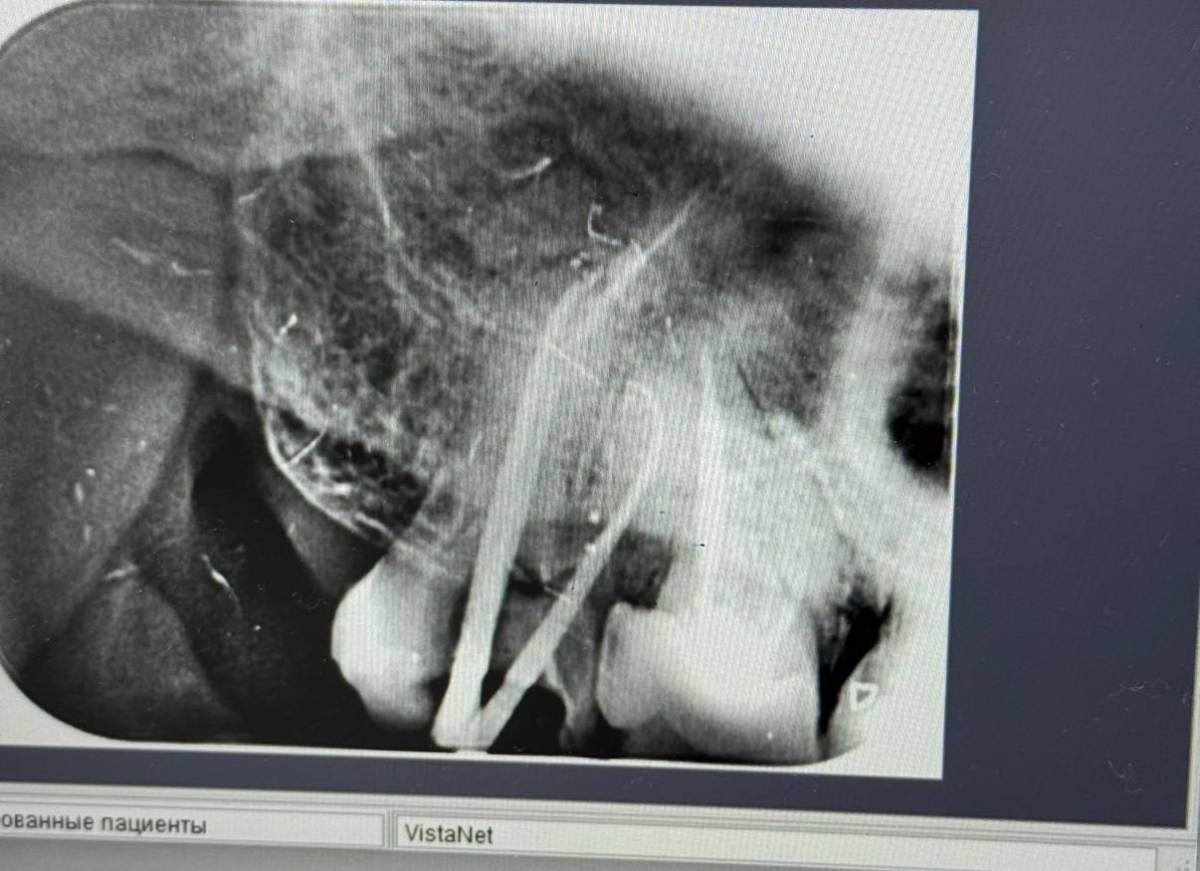

И так зуб ранее уже был леченым, небольшие неприятные ощущения все время были, чуть больше месяца назад вскрыли, последний канал долго не могли пройти, но 2 недели назад распломбировали таки, уже много раз мыли, чистили каждый раз прикрывали временной пломбой, есть кт до вскытия каналов, и есть снимок после открытия всех 3, с гуттаперчей делали снимок.

Помогите пожалуйста понять, в чем дело. из за чего сохраняется боль при накусывании, а так же если шевелить пальцами зуб в стороны (не с не с большой силой конечно же), а так же сохраняется произвольная боль в течении дня, при нагрузке физической и эмоциональной, интенсивность конечно немного меньше чем 2-3 недели назад, но она есть, я бы не сказал что прям легкая. Доктор специализируется в том числе на корневых каналах, я понимаю что боль из-за сохраняющегося воспаления, но каковы причины его, и как быть ?

photo_2025-05-18_09-32-26.jpg

photo_2025-05-18_09-32-17 (4).jpg

photo_2025-05-18_09-32-17 (3).jpg

photo_2025-05-18_09-32-17 (2).jpg

photo_2025-05-18_09-32-17.jpg